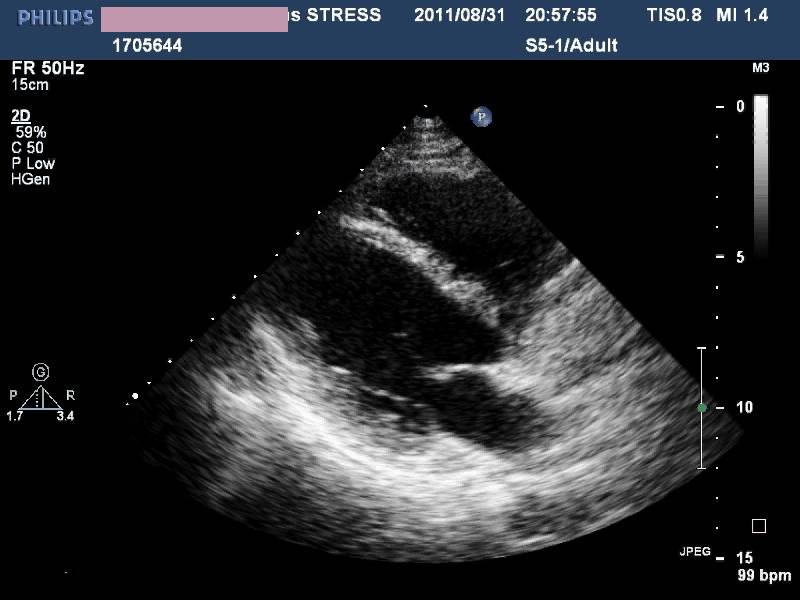

——各房室内径正常,左室收缩功能及室壁运动未见异常,LVEF 72%,少量心包积液(入院后1周)。

诊治经过-第二次心脏超声

◆感染之后出现

◆广泛心肌受累

◆初期有心肌坏死表现

◆心力衰竭

◆无心律失常

◆一周内完全恢复

——病毒性心肌炎?

应激性心肌病?